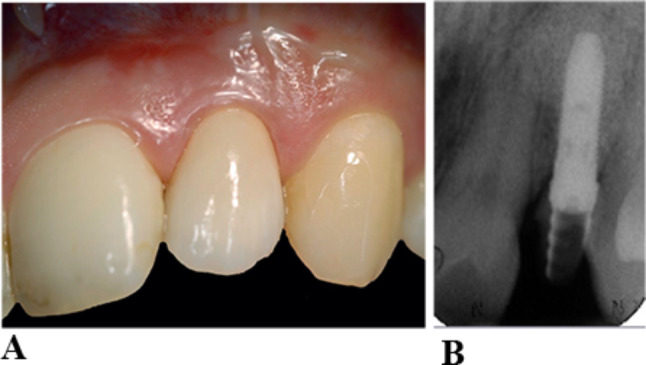

Results: The mean peri-implant crestal bone loss during the first 12 months was 1.3 ± 0.7 mm. Patients with gingival phenotype 1 had a significantly greater rate of increased crestal bone loss at implants (p = 0.016). No significant differences were present in subsequent years. The prevalence of mucositis at all implants was 27.2%, and the prevalence of peri-implantitis 9.3%. Univariate analyses indicated a significantly higher peri-implantitis risk in patients with gingival phenotype 2 (p-OR = 0.001; p-OR = 0.020). The implants of patients with phenotype 2 had significantly greater probing depths (1st year p < 0.001; 3rd year p = 0.016; 10th year p = 0.027; 15th year p < 0.001). Patients with gingival phenotype 3 showed no significantly increased probing depths, signs of inflammation and crestal bone loss.

Conclusions: Patients with a gingival phenotype 1 have greater crestal bone loss at implants during the first year of functional loading. Patients with gingival phenotype 2 had significantly greater probing depth at implants and risk of peri-implantitis.

Abstract Image